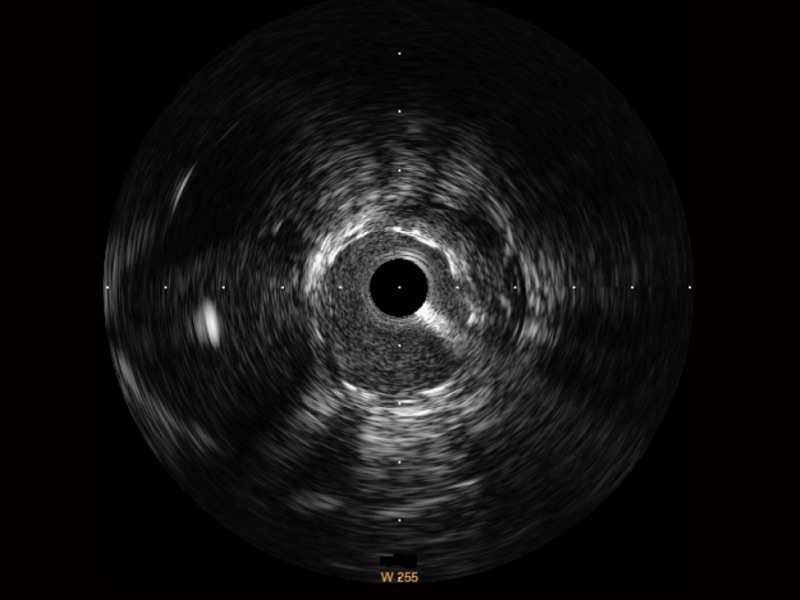

传统IVUS图像

对比传统IVUS导管成像,milan米兰宽频IVUS图像的近场支架梁显影更细腻,远场中膜外血管仍清晰可辨,兼顾远中近,兼顾分辨力与穿透深度